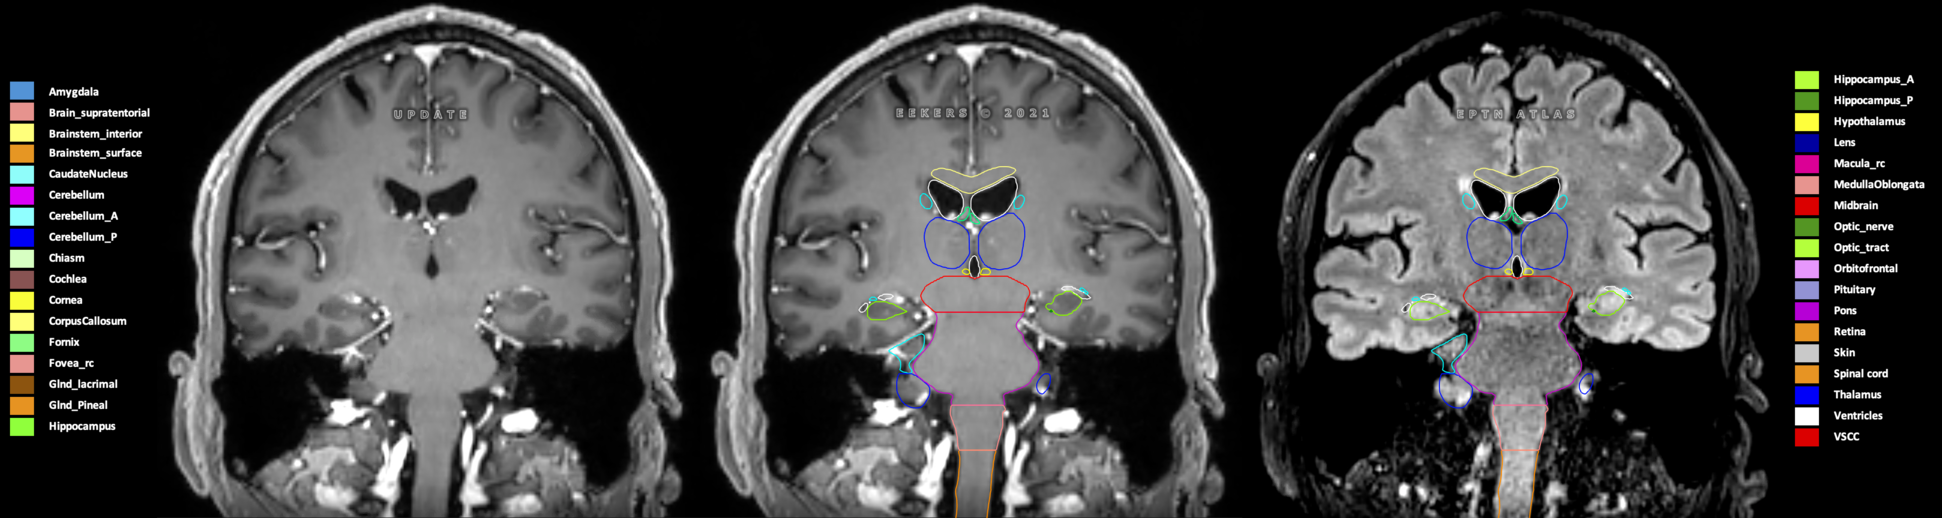

Eekers et al. have published an international neurological atlas for contouring of organs at risk in consensus with the European Particle Therapy Network (EPTN) in 2018 and an update in 2021. The purpose of this consensus atlas is to decrease inter- and intra-observer variability in delineating OARs relevant for neuro-oncology.

Included are all OARs known to be relevant for radiation-induced toxicity in neuro-oncology: brain, brainstem (midbrain, pons, medulla oblongata), chiasm, cerebellum (anterior & posterior), cochlea, cornea, hippocampus (anterior & posterior), hypothalamus, lens, lacrimal gland, optic nerve, pituitary, skin, and vestibular & semicircular canals. To further facilitate research on cognition, vision and radiological changes after irradiation of the brain, potential clinically-relevant OARs are included: amygdala, caudate nucleus, cerebellum (anterior & posterior), corpus callosum, fornix, macula, optic tract, orbitofrontal cortex, periventricular space (PVS), pineal gland, and thalamus.

Three-dimensional delineation of the 25 consensus OARs for neuro-oncology are shown on CT (WW/WL 120/40, 3000/600), 3T MR images, (T1Gd, T2FLAIR 1mm) and 7T MR (MP2RAGE 0.7 mm). All are presented in transversal, sagittal and coronal view.